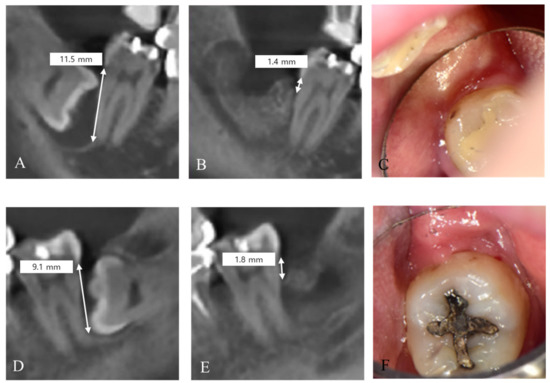

| 17 | 42 | Female | Delayed graft | 4.2 | 9.1 | 1.8 |

| 18 | 43 | Female | Delayed graft | 4.2 | 11.5 | 1.4 |